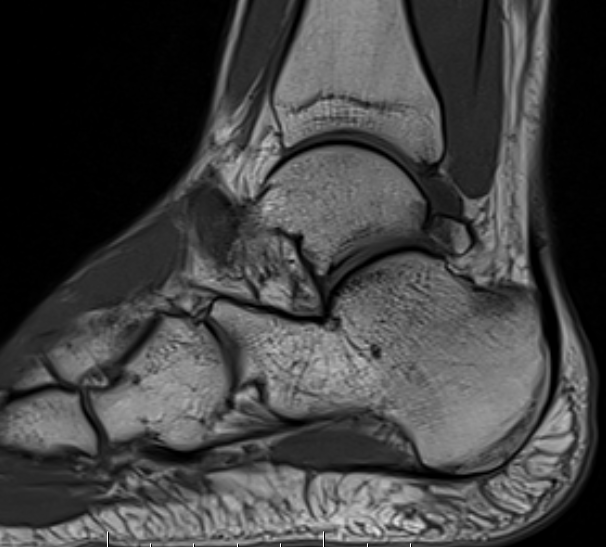

MRI

Findings

- synovitis over posterolateral process talus

- fluid in sheath about FHL

- edema around os trigonum

- edema posterior tibia bone

- thickened posterior capsule

Os trigonum FHL tenosynovitis with posterior ankle joint soft tissue

Stieda's process with ankle joint effusion